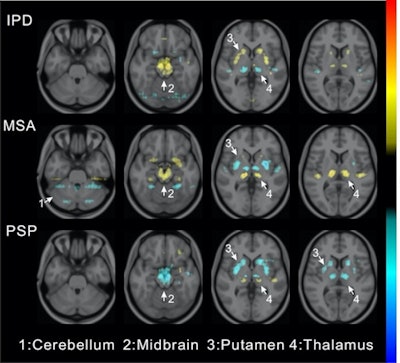

Visualization of average saliency maps of patients with idiopathic Parkinson's disease (IPD), multiple system atrophy (MSA), and progressive supranuclear palsy (PSP) in the training cohort showing characteristic regions contributing to the deep metabolic imaging (DMI) indices. The color corresponds to the importance score indicating the contribution of a region for the generated DMI indices. The color directions (yellow and red vs. cyan and blue) represent different influences on the DMI indices (increased uptake value contributes to the increase or decrease of the probability of IPD, MSA, or PSP in the DMI indices). The arrows pointed to the most salient brain regions including 1: Cerebellum, 2: Midbrain, 3: Putamen, and 4: Thalamus. Image courtesy of the Journal of Nuclear Medicine.

Visualization of average saliency maps of patients with idiopathic Parkinson's disease (IPD), multiple system atrophy (MSA), and progressive supranuclear palsy (PSP) in the training cohort showing characteristic regions contributing to the deep metabolic imaging (DMI) indices. The color corresponds to the importance score indicating the contribution of a region for the generated DMI indices. The color directions (yellow and red vs. cyan and blue) represent different influences on the DMI indices (increased uptake value contributes to the increase or decrease of the probability of IPD, MSA, or PSP in the DMI indices). The arrows pointed to the most salient brain regions including 1: Cerebellum, 2: Midbrain, 3: Putamen, and 4: Thalamus. Image courtesy of the Journal of Nuclear Medicine.The deep metabolic imaging indices extracted from PDD-Net provided an early and accurate method for the differential diagnosis of parkinsonian syndromes, with high rates of sensitivity and specificity for Parkinson's disease, multiple system atrophy, and progressive supranuclear palsy, according to the findings.